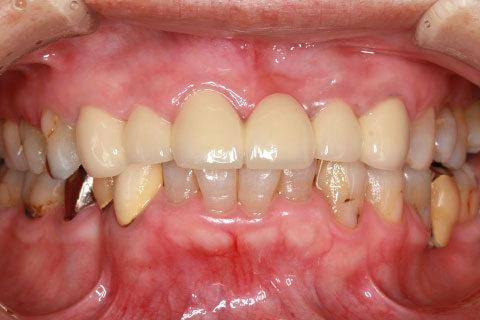

• オールセラミックの症例2

治療前

治療後

年齢・性別

45歳男性

治療期間

2ヶ月

抜歯

なし

治療費

70.4万円

備考

前歯8本の歯列不正によるセラミック治療

治療内容

歯質を削除し、セラミック冠をセメント合着

施術の副作用(リスク)

知覚過敏、歯髄炎、荷重負担